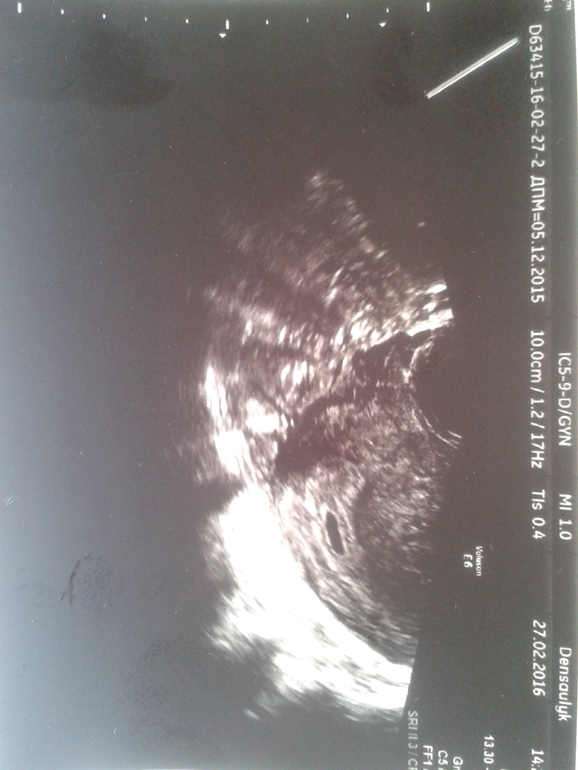

Не хотела себя накручивать сразу не пошла на узи, а сегодня любопытность моя победила,лучше б не ходила. Пошла в частный центр, сделали мне узи, ничо путнего не сказали, плодное яйцо есть, замеры не указали, типа их суперсовременный аппарат не может еще определить, форма овальная (типа деформировано), эмбриона нет. СВД 0,52. Поставили мне беременность на раннем сроке под вопросом, контроль через две недели. Может ли быть в моем случае ранний срок или уже все замерло? Насколько опасно овальное плодное яйцо для эмбриона? Напугали, что может выкинуть или замереть. Спасибо.